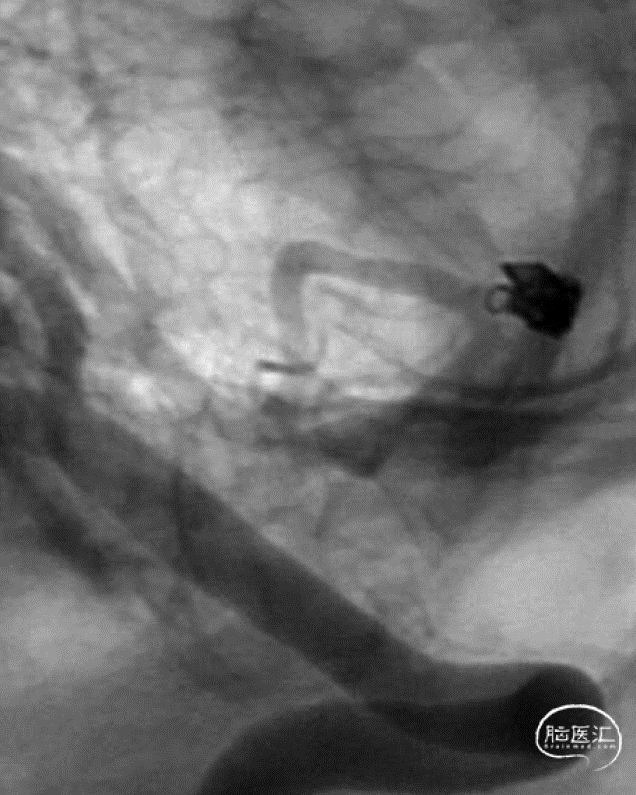

入院急诊DSA提示右侧小脑后下动脉远端动脉瘤,动脉瘤位于PICA蚓部分支

二维及三维重建提示动脉瘤形态不规则,可见瘤壁存在小泡凸起,瘤颈宽3.6mm,瘤高2.0mm,瘤体最大径2.5mm,未见血管明显痉挛

Echelon 10微导管到位

行单纯弹簧圈栓塞及载瘤动脉闭塞术。术后即刻造影提示动脉瘤不显影,载瘤动脉闭塞,侧枝代偿良好